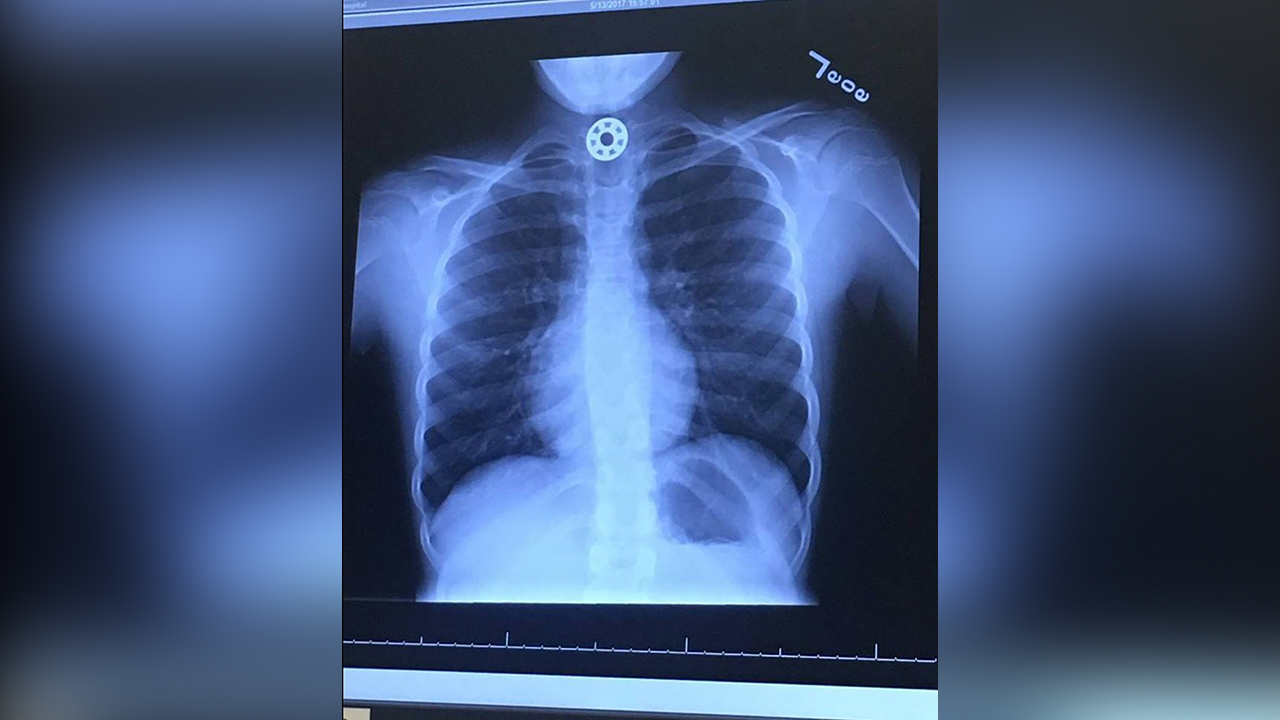

Doctors were unable to tell where the object had gotten stuck. It wasn't until after an ambulance ride to Texas Children's Hospital that an X-ray revealed the round metal bearing in the girl's esophagus.